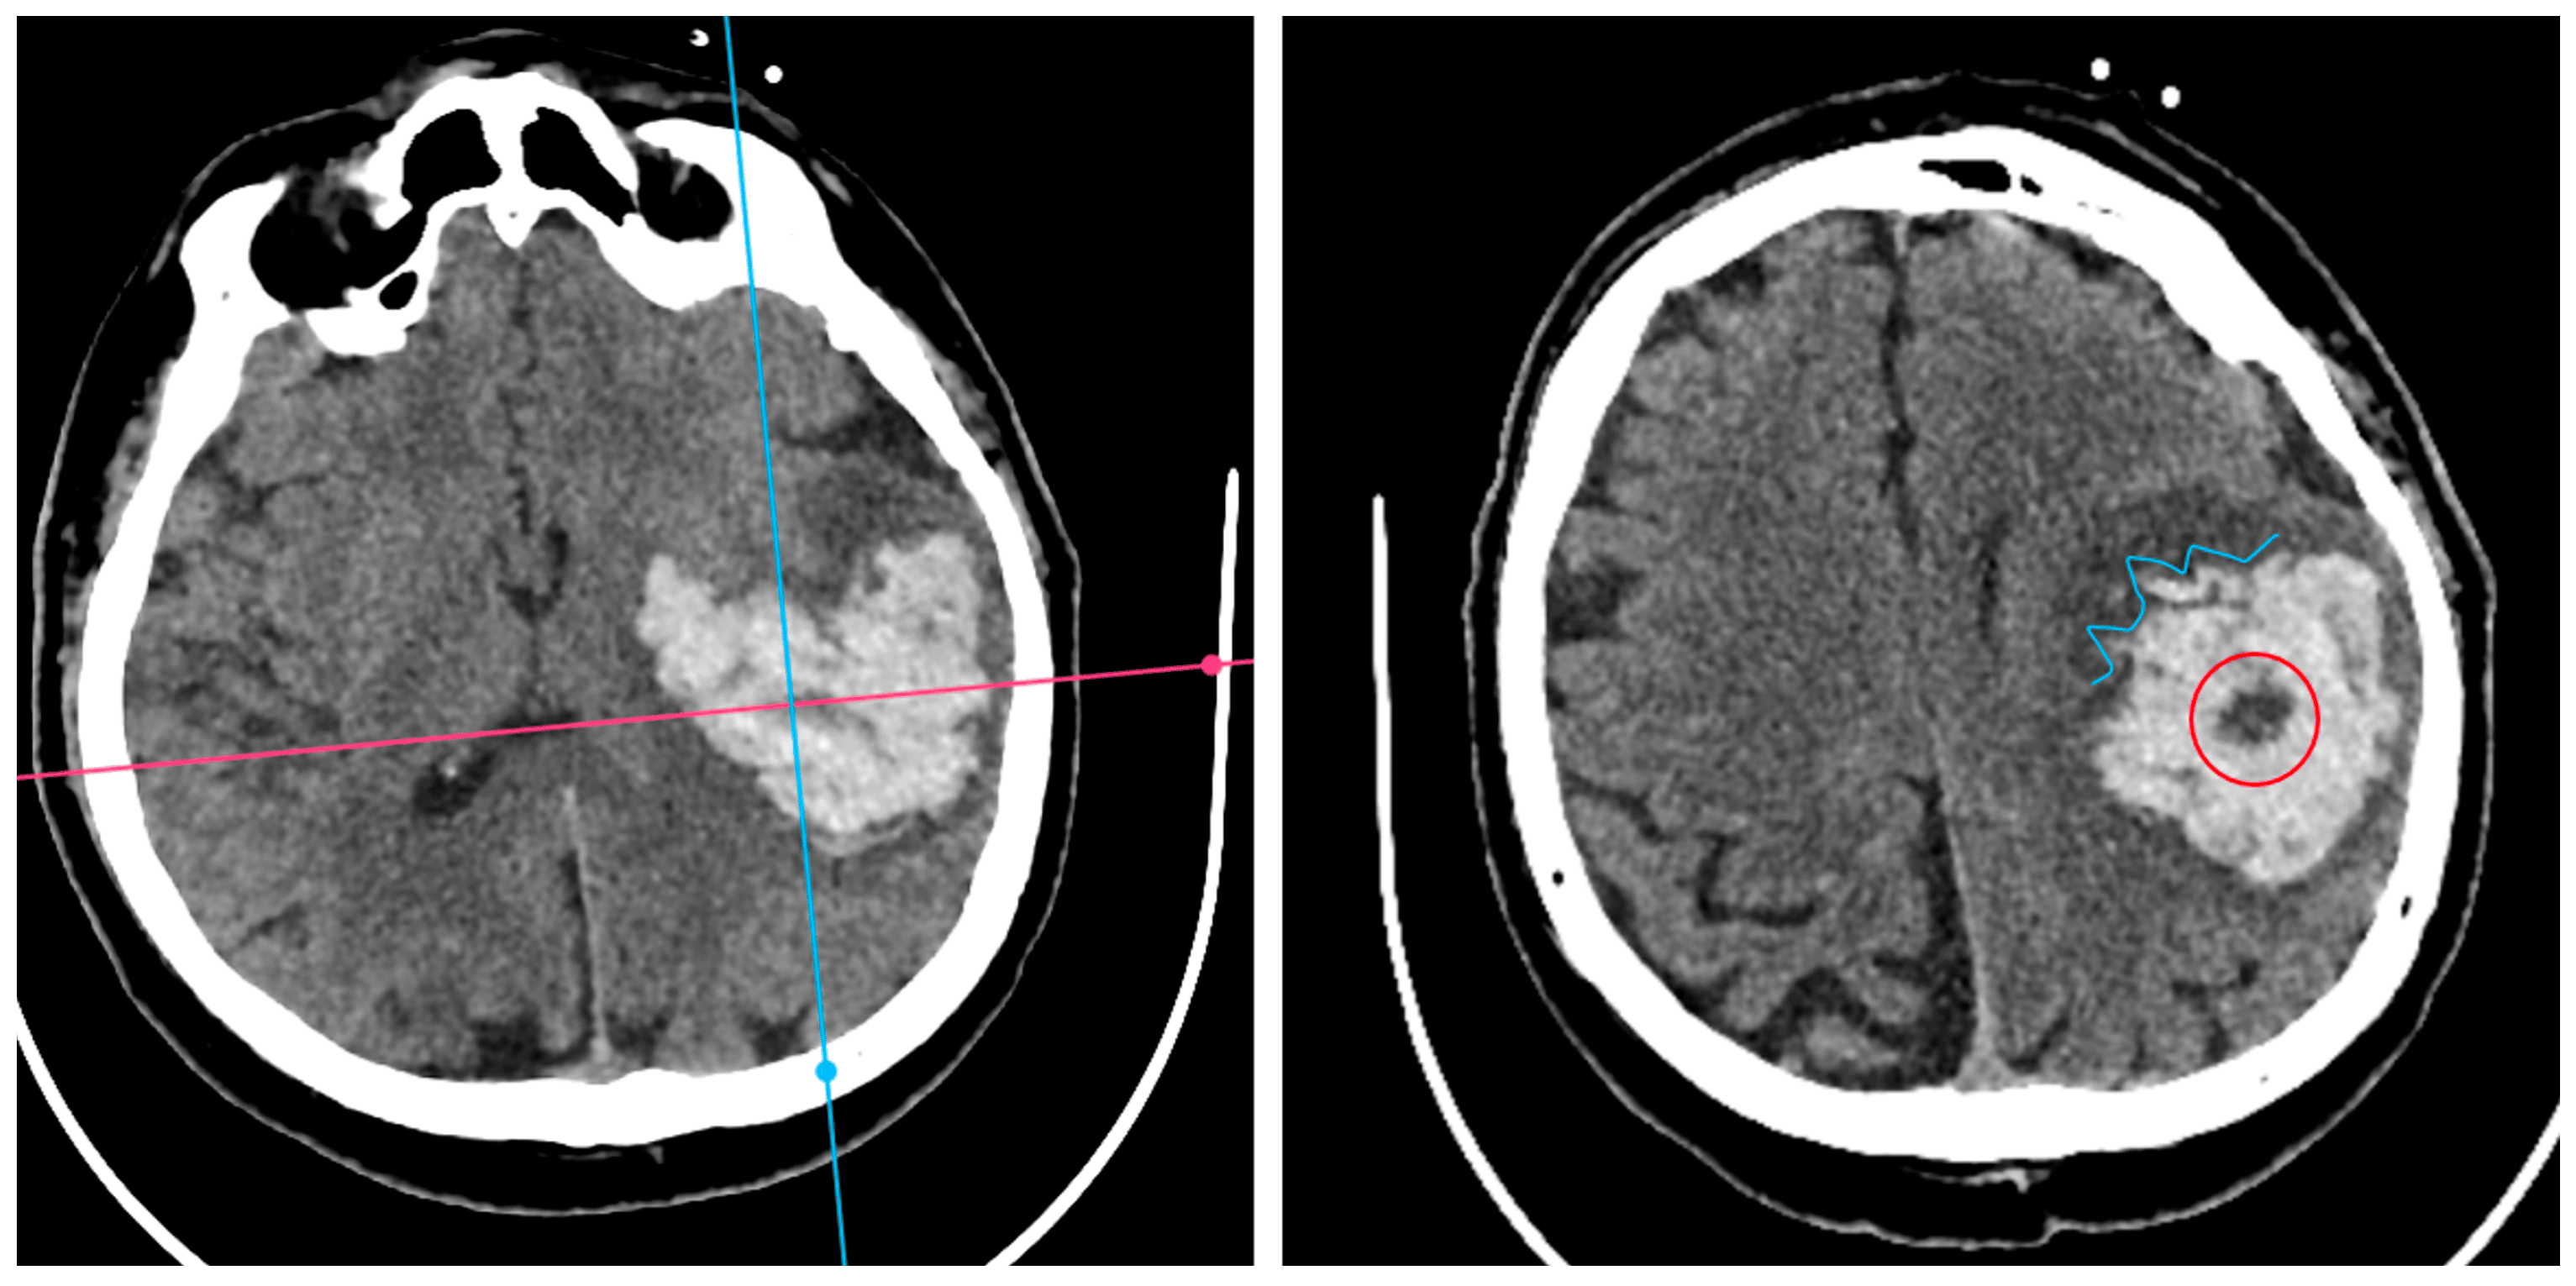

Below is an illustrative breakdown of hematoma expansion according to the presence of each NCCT sign on baseline imaging. In this dataset, 89 out of 404 patients (22.0%) demonstrated significant enlargement (“YES”) on follow-up CT, whereas 315 (78.0%) did not progress (“NO”). Table 2 shows that all four radiological signs were substantially more frequent among those with hematoma expansion. Notably, the Black Hole Sign (BHS) has the most pronounced association with expansion, affecting 56.2% of patients in the “YES” group versus 23.8% among “NO” cases (p<0.001 by chi-square). This observation reinforces the concept that a distinct hypodensity within the main clot may reflect ongoing or repeated hemorrhage, placing the patient at higher risk of volume growth.

Despite these robust associations, several limitations warrant consideration. Early surgical evacuation in some patients may have led to underestimation of expansion, while late presentation could mean that signs such as the Blend Sign reflected a post-expansion state rather than a purely predictive marker. Additionally, “slightly irregular” shapes can be subjective. Overall, however, the Black Hole Sign appears most strongly correlated with hematoma enlargement, underscoring its potential as an indicator of ongoing bleeding risk (Figure 5).

Figure 5. Left: ICH with expansion with the presence of BHS and IRS; Right: ICH without hematoma expansion, no NCCT Signs observed